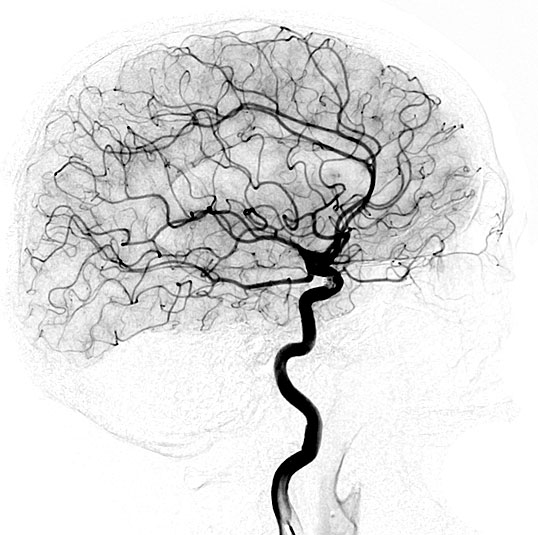

TCD-LA provides clinicians with a real-time assessment of physiological flow within the intracranial arteries that may improve outcomes in both inpatient and outpatient settings.

TCD Complete

All the vessels of the Circle of Willis are evaluated.